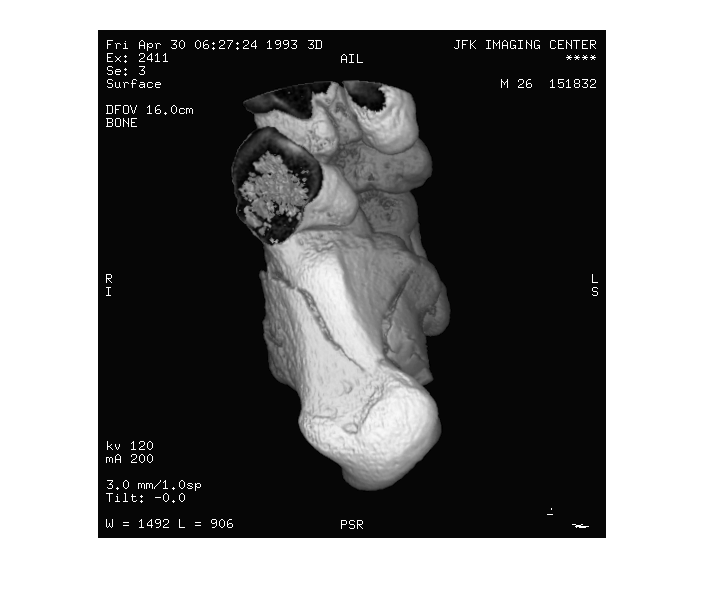

Считайте изображение из файла DICOM и отобразите его с помощью imshow.

info = dicominfo('CT-MONO2-16-ankle.dcm');

Y = dicomread(info);

figure

imshow(Y,[]);

Figure contains an axes. The axes contains an object of type image.